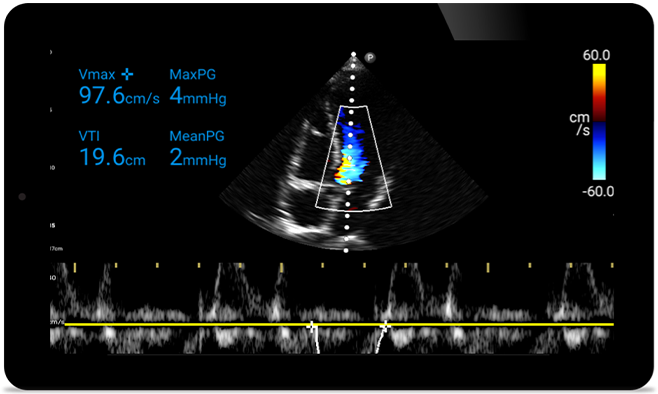

Acţionaţi mai repede pentru le proteja inima

Atunci când secundele contează, ecograful portabil poate face diferenţa. Lumify vă poate oferi imaginile de înaltă definiţie de care aveţi nevoie oricând şi oriunde aveţi nevoie.